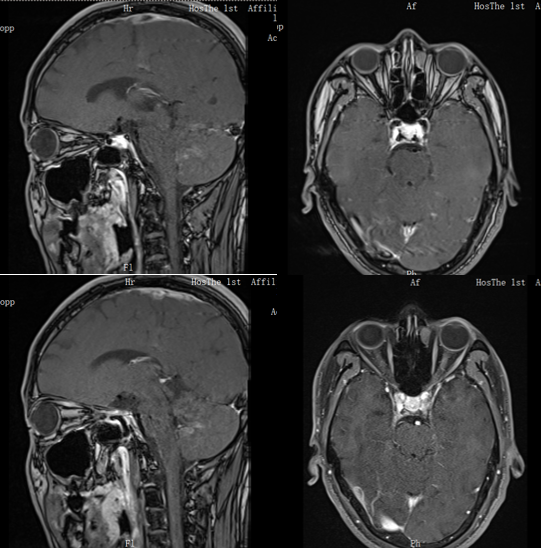

• 影像学检查:头颅+全脊髓+视神经MRI:四脑室周围双侧小脑半球、延髓、右侧侧脑室旁及颈5-7水平脊髓内异常信号;左侧视神经眶内段、管内段及双侧视神经颅内段异常信号,结合病史,考虑为NMOSD。

图1 患者头颅MRI平扫+增强

图3 视神经MRI平扫+增强